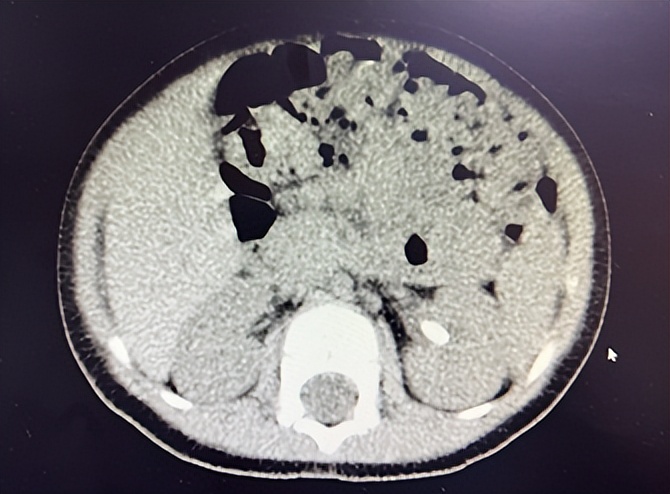

由于疫情反复,齐齐和爸妈等了两周才来到北京大学国际医院,泌尿团队立即详细检查,发现不到2岁的齐齐结石在X线下显影不佳。儿童泌尿系结石领域专家贾建业教授专程从上海进京,共同研究诊疗方案,最终决定采取以B超为主、结合X线双重定位的碎石方式。

2022年09月22日早,齐齐在麻药的作用下沉沉地睡去。贾建业教授在B超的辅助下熟练操作碎石机,将齐齐体内的结石精准击碎。

贾建业教授为齐齐治疗时始终保持着俯身、轻托的姿态,这是她多年经验总结的“mama holding baby”(爱心妈妈托举结石宝宝)独特方法。她不断微调、追踪冲击波焦点,随着结石面积不断扩大,定位改为X线,更加快捷地击碎已经脱离原位的碎块。

整个碎石过程20余分钟,齐齐麻醉苏醒后在父母的陪同下返回病房。中午时分,病房传来消息——齐齐已经排出泥沙样的结石。

手术中